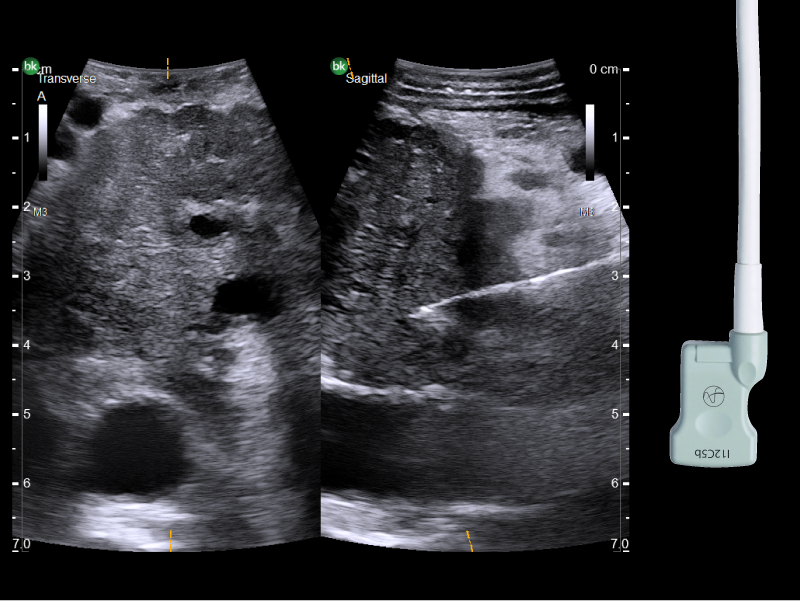

Visualize hepatic and pancreatic tumors and surrounding anatomy throughout the procedure

Active imaging supports liver and pancreas tumor resection procedures by helping you visualize complex anatomical variations and relationship to vascular structures, identify tumor location, define adequate margins of resection, and assess surgical planning.